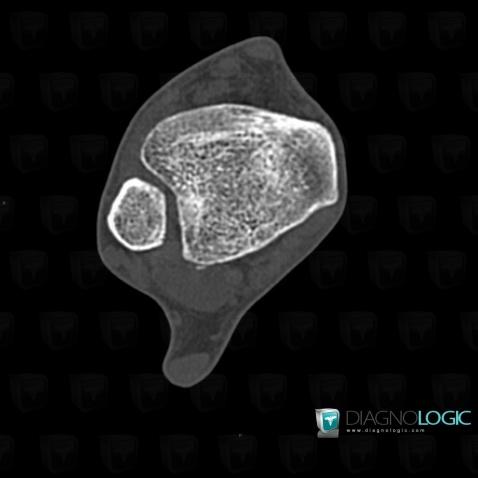

Lateral collateral ligament tear / Ankle, Lateral collateral ligament - Ankle, CT

Here is the specific information in the key image above:

- Diagnosis Lateral collateral ligament tear / Ankle, Location(s) Lateral collateral ligament - Ankle, with gamuts Ankle ligament injury